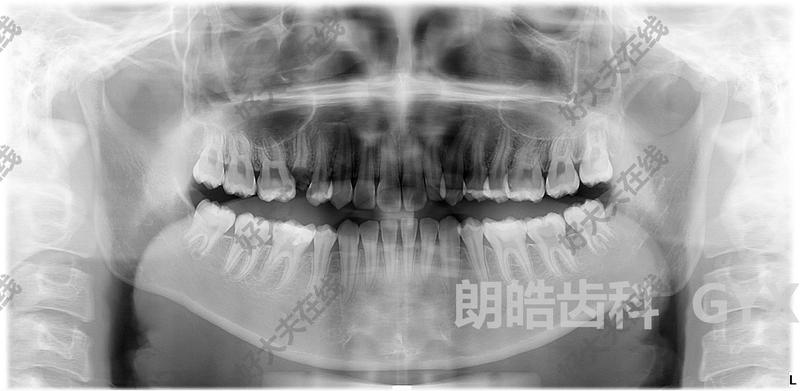

看了這張圖,還敢說乳牙蛀牙不用補?

有老觀點認為“乳牙蛀了不用補,等著換牙就好了",殊不知嚴重的乳牙蛀牙也會影響恒牙。兒童齲齒預防大于治療,家長們要注意孩子的口腔衛(wèi)生,每天2-3次刷牙,每次2分鐘,6周歲以下的兒童需要家長幫忙刷牙。兒童需每3個月或6個月到口腔科做全面檢查,及時做涂氟,窩溝封閉等預防齲齒。